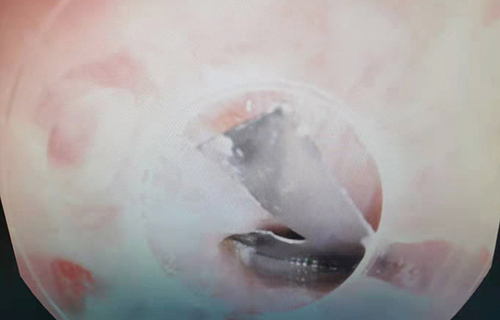

手术前,边鹏对异物的情况进行了充分研判,考虑到刀片的锋利性,摘取过程中如稍有不慎,就可能划伤食道,造成二次损伤。边鹏在异物钳前端加了一个透明帽,以保护食道。当食道处的刀片被顺利取出后,边鹏又将内镜探入女孩胃部,继续寻找异物。由于胃内存有不少食物,镜下探寻难度极大。期间,边鹏利用异物网兜,反复进行捞取,最终,在女孩胃部的一个角落里发现了刀片,并顺利取出。

整个过程用时15分钟,取出2枚长度分别为2.5厘米和1.5厘米的刀片。这一刻,所有人悬着的心终于落地了。由于异物在女孩食道和胃部留存了3个多小时,食道黏膜略微糜烂,边鹏给予盐水冲洗处理。